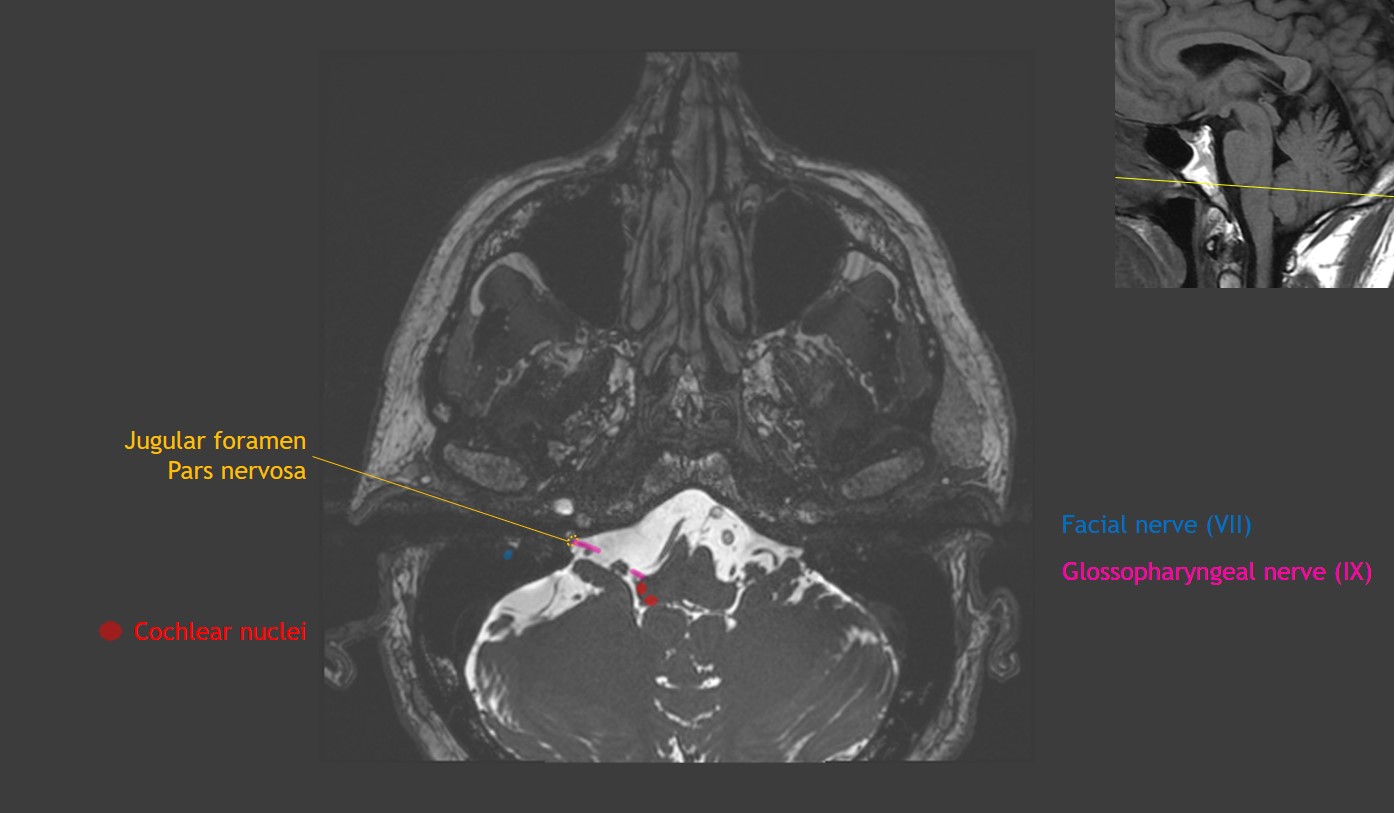

Anatomy and Imaging of the Cranial Nerves: A Neuroanatomic Method of Investigation Using Magnetic Resonance Imaging (MRI) and Computed Tomography (CT)

Anatomy and Imaging of the Cranial Nerves: A Neuroanatomic Method of Investigation Using Magnetic Resonance Imaging (MRI) and Computed Tomography (CT)

Anatomy and Imaging of the Cranial Nerves: A Neuroanatomic Method of Investigation Using Magnetic Resonance Imaging (MRI) and Computed Tomography (CT),

Anatomy and Imaging of the Cranial Nerves: A Neuroanatomic Method of Investigation Using Magnetic Resonance Imaging (MRI) and Computed Tomography (CT), Cranial Nerve Anatomy on MRI | CaseStacks.com,

Cranial Nerve Anatomy on MRI | CaseStacks.com, Cranial Nerve Anatomy on MRI,